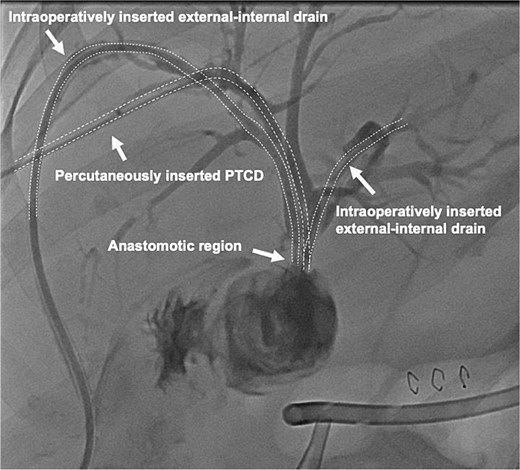

A 64-year-old obese woman presented to the emergency department with clinical signs of cholestasis. Initial imaging identified cholecystolithiasis and bile duct dilatation, later confirmed as choledocholithiasis visualized on endoscopic ultrasound. Subsequently, the patient underwent ERCP with papillotomy, stone removal and stent placement. Seven weeks later, an elective laparoscopic cholecystectomy was performed. Severe inflammation of the surrounding tissue was noted intraoperatively. The gallbladder was shrunken and embedded within the liver parenchyma, hindering the critical view of safety. On the first postoperative day, significant bile leakage of 400 ml was observed prompting an immediate exploratory laparoscopic revision by our hepatobiliary team. Here, a transection of the extrahepatic bile duct just above the hepatic duct confluence was detected, resulting in three separate ostia: two on the left side (left main duct and segment IV bile duct) and main right hepatic duct. To reconstruct the biliary anatomy the procedure was converted to open surgery. The two left-sided bile ducts were joined together by two interrupted stiches to create a common channel for the Roux-Y-hepaticojejunostomy. The right-sided duct required a separate HJ 3 cm proximally on the same jejunal limb. To prevent bile leakage and stenosis two external-internal biliary drains were placed in the left-sided anastomosis, routed transhepatically and ending in the jejunum (Fig. 1). Due to technical challenges related to the patient’s obesity a third external-internal biliary drain could not be placed in the right-sided HJ. The biliodigestive anastomosis was constructed with an interrupted absorbable 5/0 monofil sutures in duct-to extra mucosal technique.

Conjunction of the left-sided bile ducts into a single hepaticojejunostomy. The right-sided duct required a separate hepaticojejunostomy using the same jejunal limb. To prevent complications, transhepatic external-internal biliary drains were placed in the left-sided anastomosis, extending into the jejunum.

On the following day, a percutaneous transhepatic cholangiography drainage (PTCD) was placed in the right duct via interventional radiology for additional bile drainage support (Fig. 2). The patient was discharged on postoperative day 16 with the three closed drains in place. Four weeks later, she was readmitted for drain removal, with imaging (Fig. 3) and laboratory results (total bilirubin 8.4 μmol/L (norm <17 μmol/L) showing no signs of stenosis or leakage. After a follow-up of 18 months, the patient is in good condition with no clinical signs of late biliary complications.

Contrast-enhanced image of the intraoperatively inserted external-internal drains and the percutaneous transhepatic cholangiography drainage (PTCD) which was interventionally inserted into the right duct on postoperative day one.